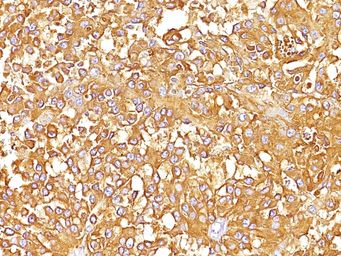

IHC-P analysis of human melanoma tissue using GTX34834 Melanoma gp100 antibody [SPM142].